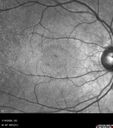

Most viewed - Acute Retinal Pigment Epitheliitis (Maybe)

15 year old male - There was a spot in the central vision in the right eye which has not been improving. Still sees a spot in the vision. Late June 2025 (7 months ago) he woke up with a spot in the central vision in the right eye that has not gone away. Eczema treated with dupixant. There have been no laser exposures (he does shoot clay but no lasers involved). He uses topical steroids intermittently for flares (about once a week). Medical Hx: Eczema. Surgical Hx: Noncontributory. Systemic Meds: Dupixent. VA OD: Dsc20/32 VA OS: Dsc20/16 IOP: TP: OD:16 OS:14

Acute Retinal Pigment Epitheliitis (Krills disease)3 views15 year old with sudden central vision loss in one eye. The vision loss persisted though for at least 6 months (which may be a laser injury)